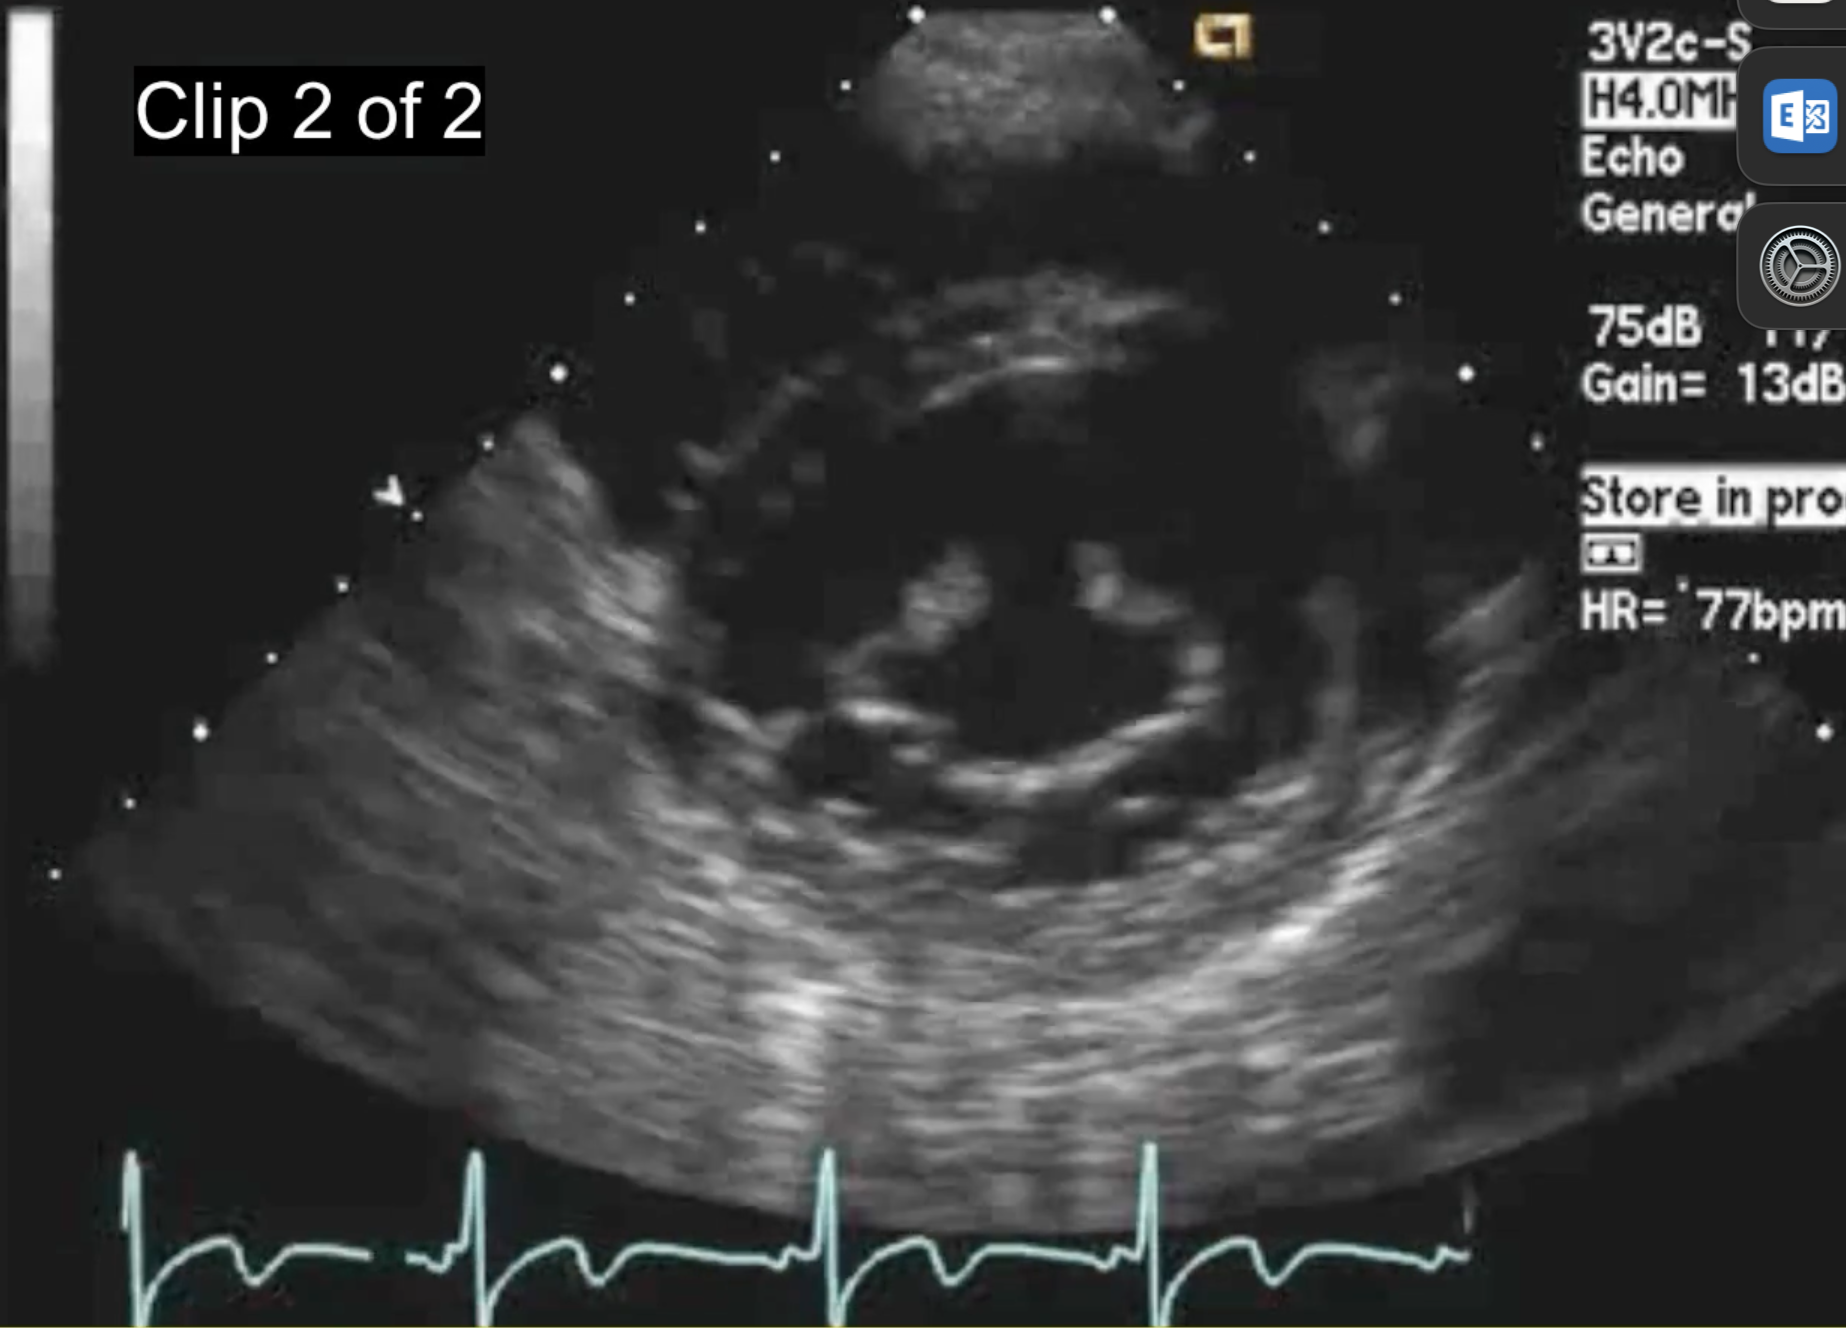

What would the immediate consequences of this be?

Eccentric anteriorly directed severe MR.

What does this show? What symtoms

-congenital cleft MV